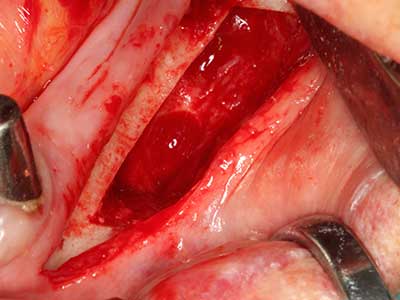

Костната тъкан е не само минерализирана структура, тя съдържа и съществено количество колагенови влакна. Това означава, че тя има не само добра компресивна сила, но и известна степен на гъвкавост, която може да се възприеме като предимство при извършване на костна аугментация. В класическата процедура по разширяване чрез костно разделяне, атрофиралият алвеоларен гребен е разделен надлъжно и внимателно разширен след достигане на подходящата остеотомна дълбочина (Фиг. 13-16), в идеалния случай без допълнително отстраняване на периостеума (Brugnami, Caiazzo et al. 2014, Stricker, Fleiner et al. 2014). Системите с винт и пластини с увеличаване на разстоянието при разширяване са доказали ефективността си при разделяне на двете костни ламели, оставайки под прага на фрактурите. В общи линии, оставащата ширина на костта от поне 3–4 mm е задължителна (Chiapasco, Zaniboni et al. 2006), за да се гарантира добра гъвкавост и достатъчно костно покритие за бъдещото поставяне на импланти. Ако е необходимо, вертикалната остеотомия на едната или двете страни може да подобри гъвкавостта. Комбинацията с допълнителни техники за аугментация, особено в букалната страна, е описана като алтернатива на класическата техника.